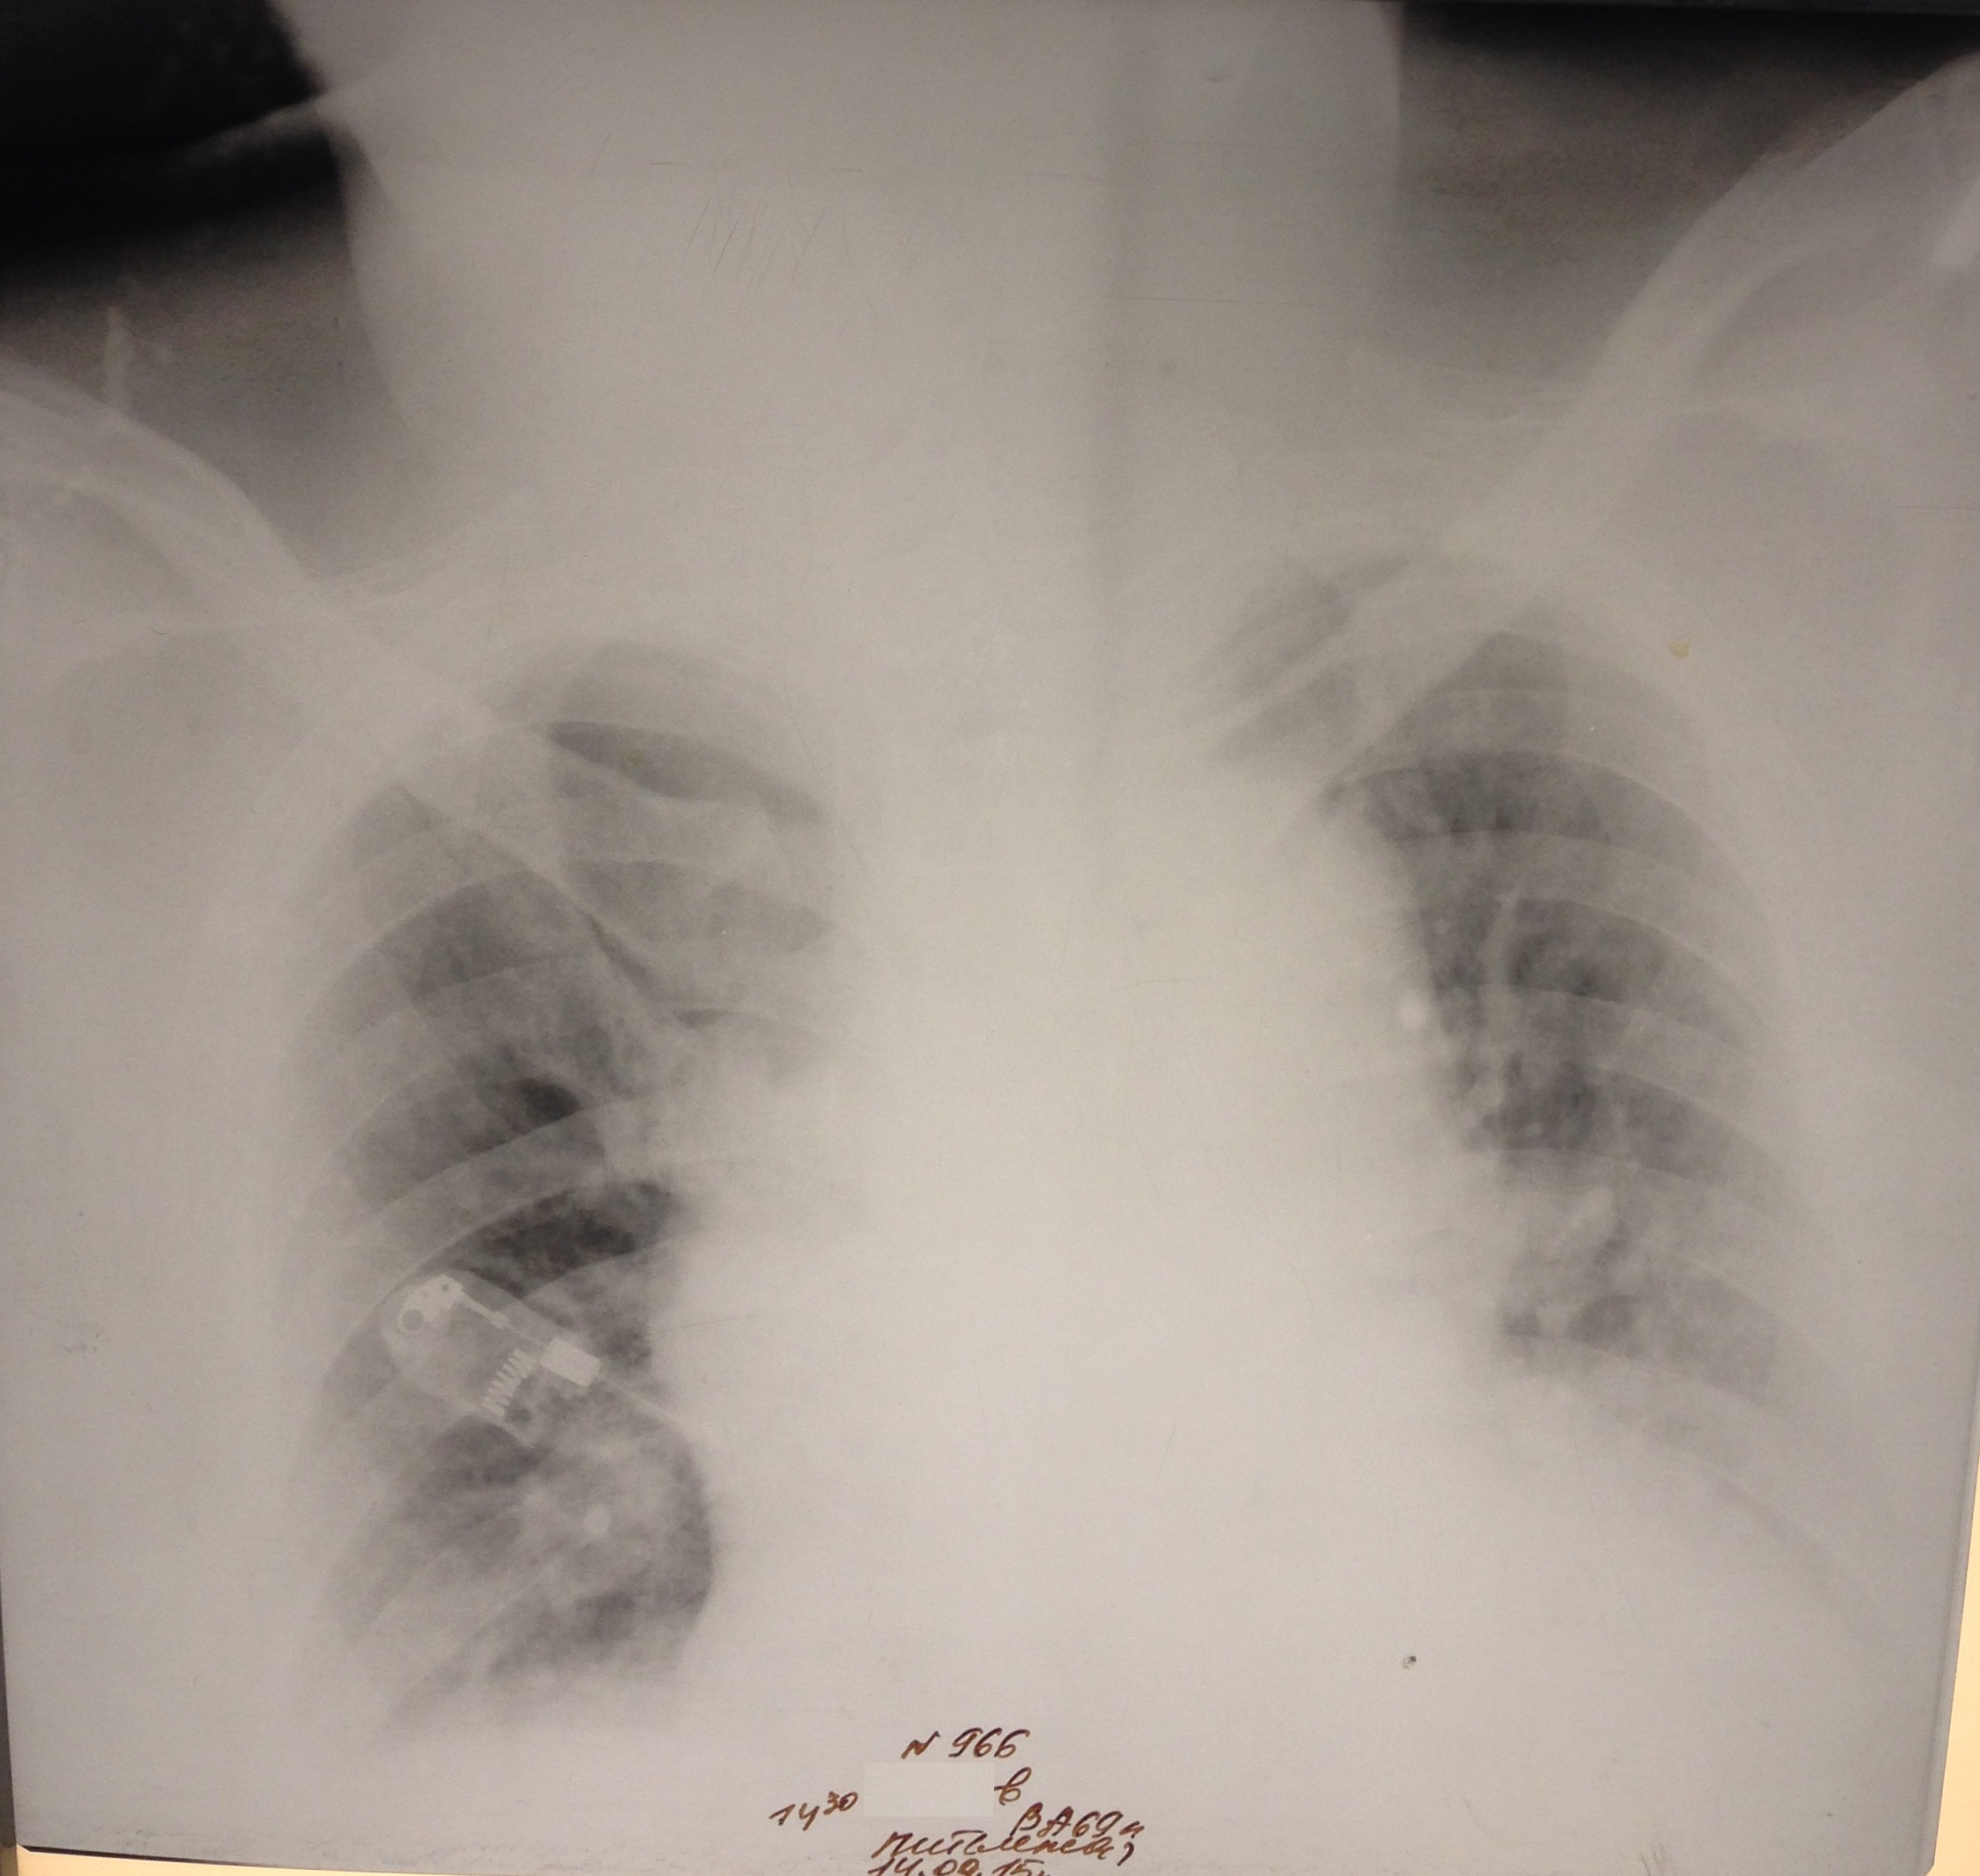

М, 69 лет. РАА. На первом снимке расширение срединной тени. На втором гемоторакс в результате прорыва крови из аорты в плевральную полость.